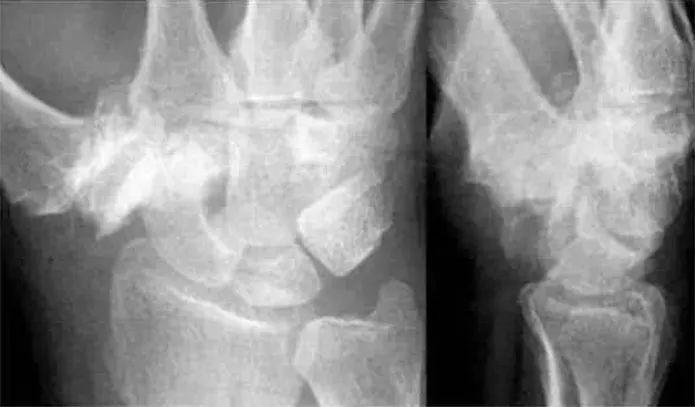

侧位显示月骨向掌侧倾斜

Case 分析

1.月骨-三角骨间隙平行关系缺失致掌骨弧线I and II中断。

2.月骨和舟骨平行,而与其他腕骨不平行。

3.舟骨缩短提示向掌侧倾斜。

4.月骨平行于舟骨,其三角形状提示为掌侧倾斜所致。

5.近排腕骨不是一个整体,因为弧线I中断。

诊断:掌屈不稳伴月骨-三角骨关节脱位